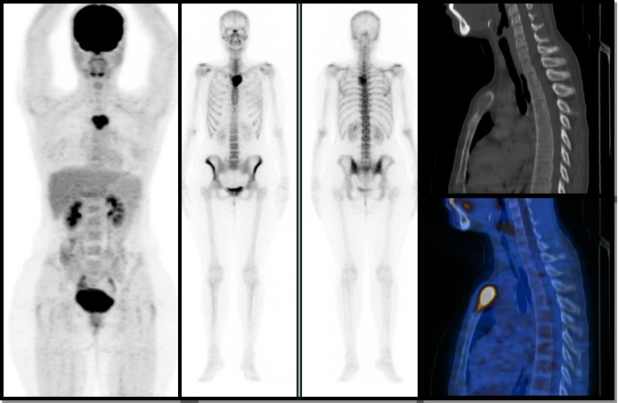

Figura 1.

Figura 1. Paciente de 55 años, con diagnóstico de cáncer de mama ductal infiltrante metastásico de 12 años de evolución. Las diferencias en la resolución y detección de lesiones óseas son notables al comparar la proyección de máxima intensidad del PET-CT (izquierda) con el rastreo óseo (derecha), siendo mucho mayor la sensibilidad para el primer método. De acuerdo a los hallazgos tomográficos, las lesiones óseas encontradas eran mixtas.